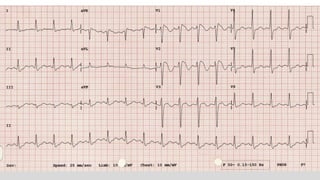

This document discusses various cases of collapse and syncope. It defines collapse as transient loss of consciousness with loss of postural tone and full recovery. Syncope is defined as loss of postural tone with or without loss of consciousness and full recovery. It then discusses the multiple potential causes of collapse and syncope including toxicological, cardiac conduction abnormalities, structural cardiac issues, autonomic dysfunction and more. It then goes through 9 case examples, discussing important questions to ask, potential tests and interventions for each case.